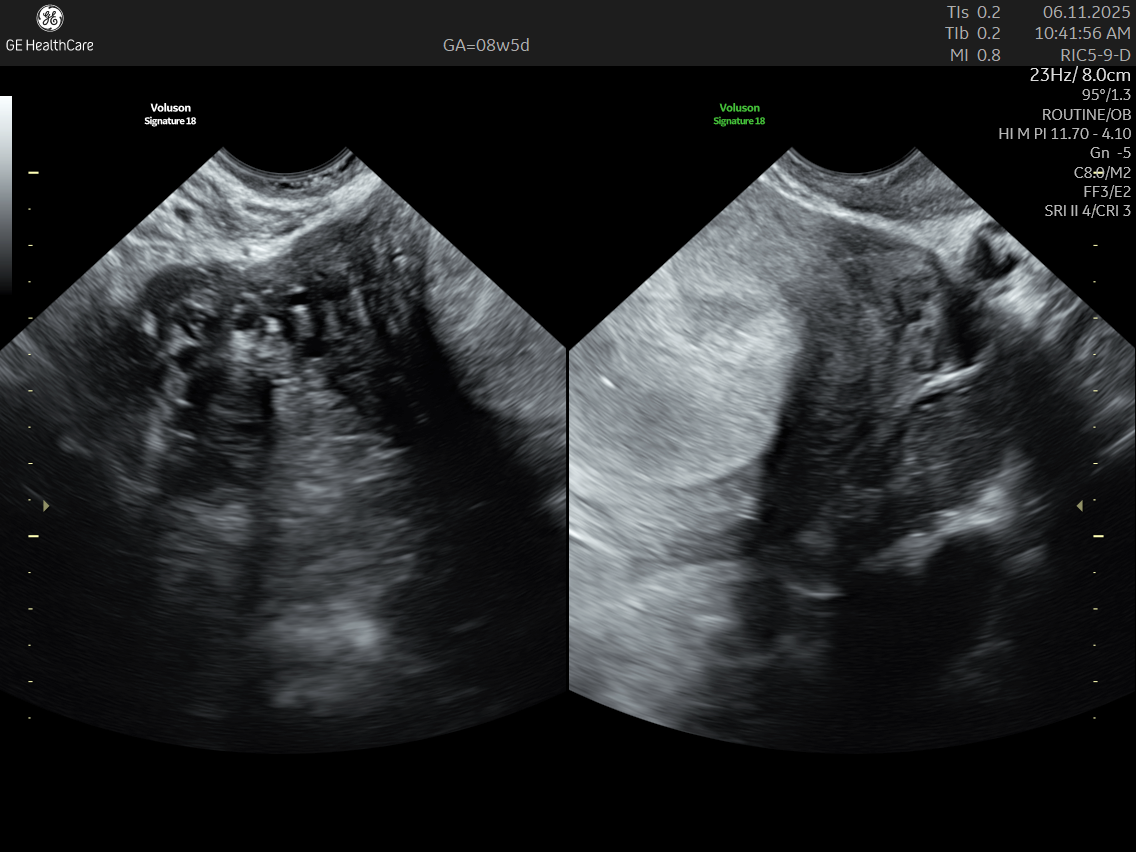

A Dating and Viability Scan is the first critical ultrasound in your pregnancy journey. Performed between 6 – 8 weeks, it confirms your pregnancy’s health, establishes how far along you are, and ensures an accurate start to your prenatal care.

- Usually conducted transvaginally for clear imaging

- May use a transabdominal approach in certain cases